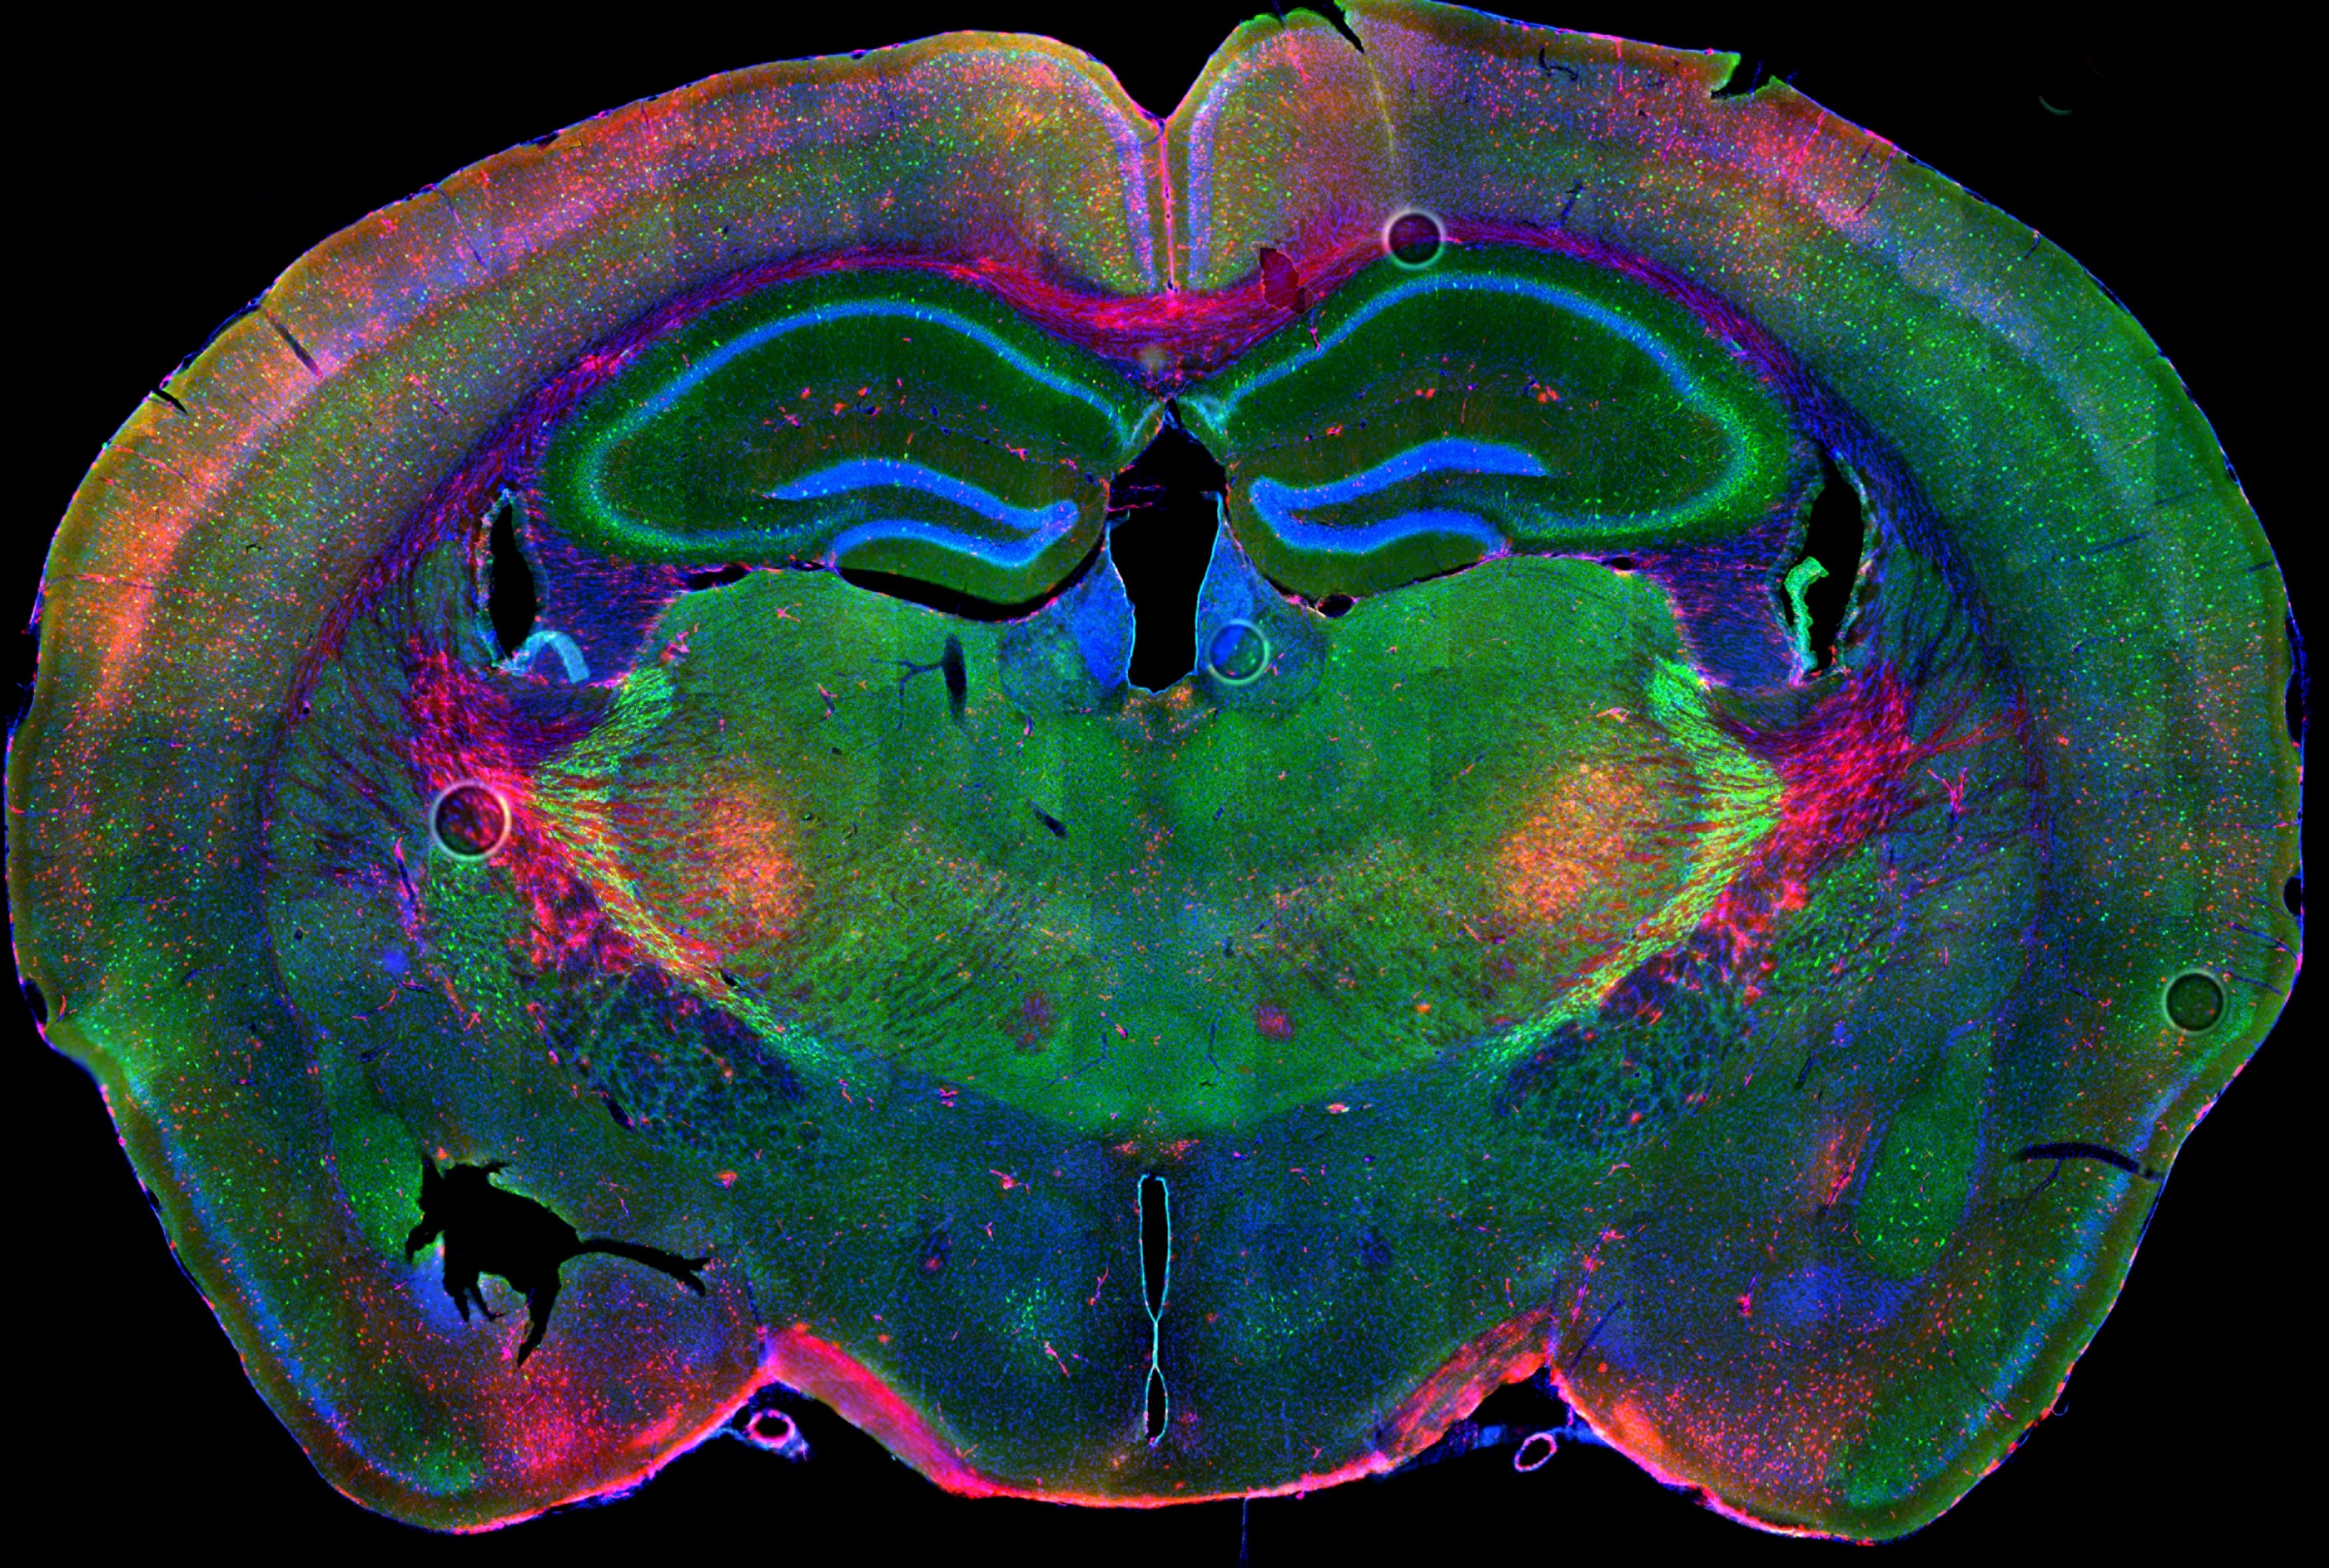

Immagine seminario interno 8 ottobre

Decoding the Function of PTEN in Autism